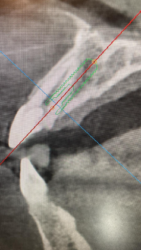

• For immediate implants, i’ve seen videos where it was mentioned to use a Linderman drill at 2000rpm to make an initial slot to prevent the slope of the extraction socket from deflecting the drill. This is in regards to anterior teeth as well as upper premolars where you are aiming for lingualized positioning

I had two questions about this